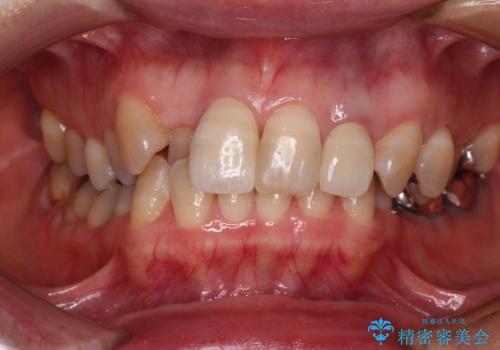

歯に独特の縞模様があり、さらに特徴的な色合いであったため、コンポジットレジンによる修復では対応が困難でした。

オールセラミッククラウンは周囲の歯よりもやや白く製作し手降りますが、今後はご自身でホワイトニングをして明るい色調で整えるとのことでした。